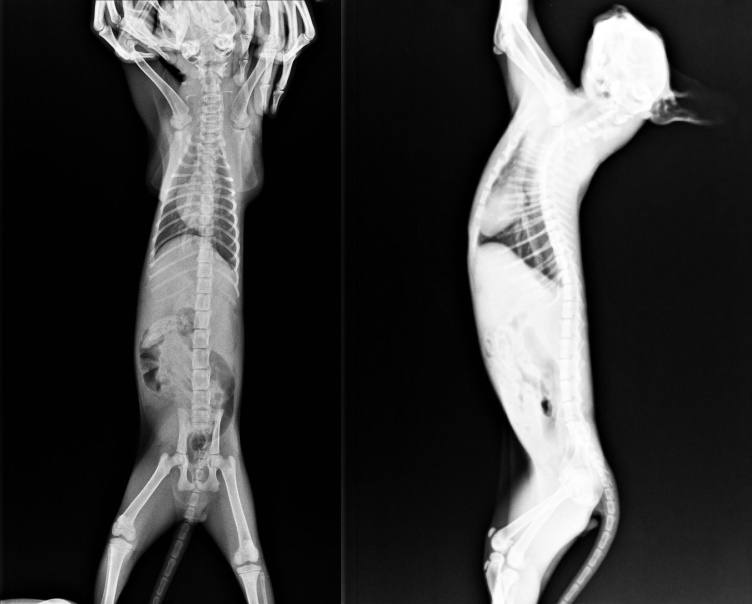

小乖鼻氣管炎最嚴重,其他兄弟姊妹都陸續出院,只剩他還在醫院隔離治療,4/22小乖狀況急轉直下,整個軟趴趴,完全沒有活力,驗血白血球34100,感染嚴重,尿毒指數130、CRE 8.5,急性腎衰竭,趕緊給與靜脈輸液,鼻氣管炎狀況更加明顯,鼻膿眼睛快要睜不開,狀況極糟,在24小時夜間看護下指數慢慢往下降,4/25已恢復正常值,但鼻氣管炎仍需長時間治療,等狀況穩定已先將小乖帶回調養照顧,目前還是有點淚眼噴嚏,但精神食慾良好,醫療費用還請各位幫忙。